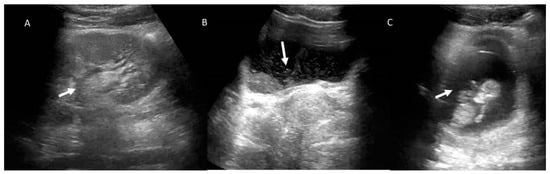

4. Clinical Setting: Abdominal Pain

5. Acute Appendicitis